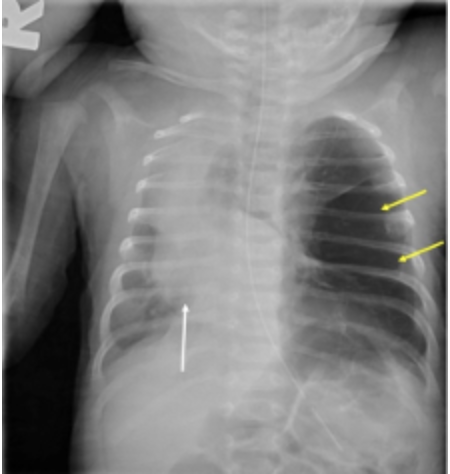

B) is incorrect as congenital diaphragmatic hernia (CDH) presents with severe respiratory distress, scaphoid abdomen, and X-rays show bowel loops in the thorax.